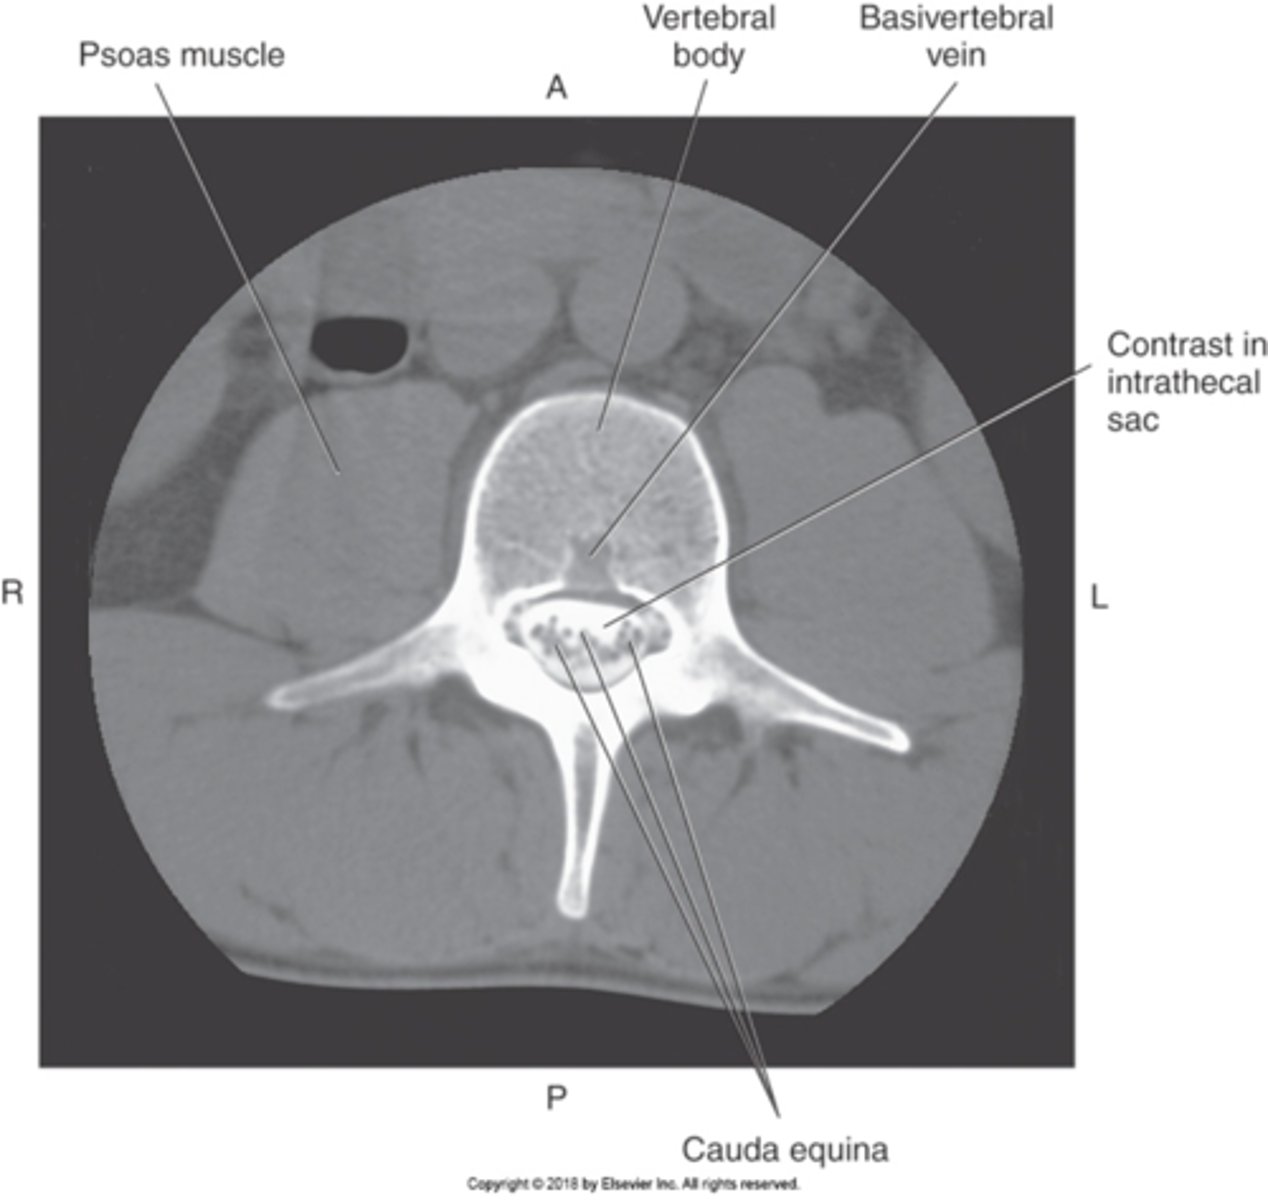

1) Psoas muscle

2) Vertebral body

3) Cauda equina

Name all numbered structures

L5 because of the bifurcation of the aorta

What vertebral level is this and how could you tell